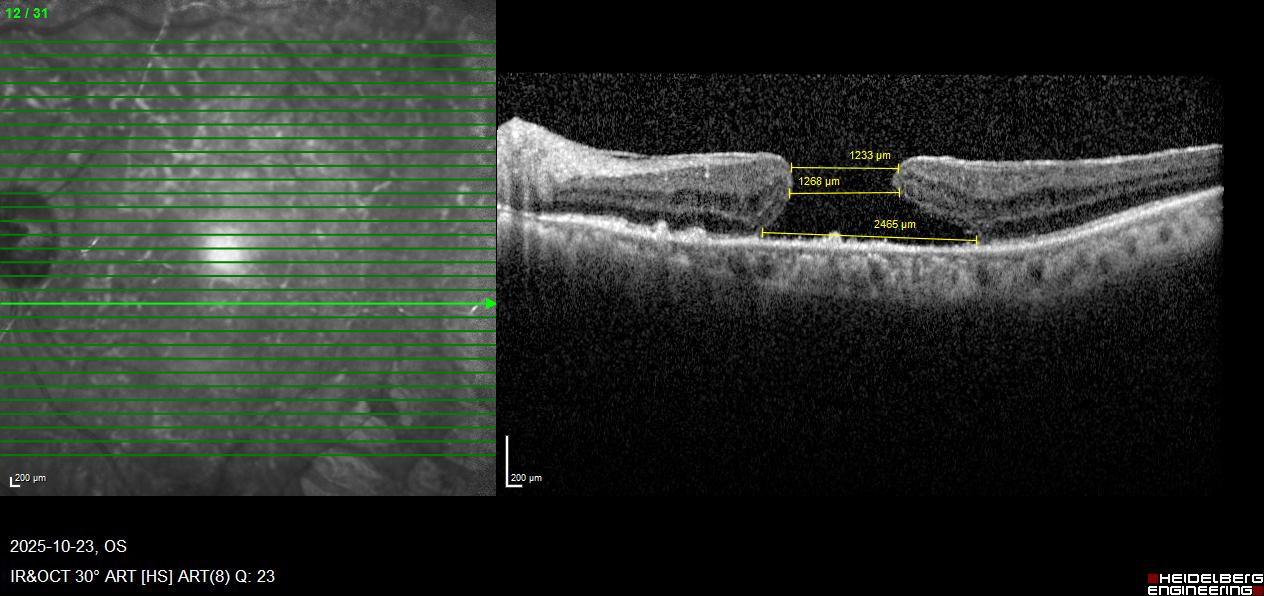

2025年杨女士再次感觉左眼视力下降,开始怕折腾繁忙工作中的孩子,半年后生活明显受限,当地眼科检查发现左眼黄斑裂孔,裂孔最窄处也超过了1200微米,医师告知她还得需要多次手术治疗,患者处于崩溃的边缘。经多方打听,杨女士了解到德州爱尔眼科医院在复杂眼底病及黄斑裂孔手术方面拥有前沿技术。抱着一线希望,她来到了德州爱尔眼科医院。

接诊的是德州爱尔眼科医院院长、眼底病专家张士玺教授团队。经过全面的OCT(光学相干断层扫描)等精细检查,张院长发现,患者的黄斑裂孔不仅直径较大,裂孔周边同时伴有继发性前膜牵拉,进一步进展将发展为黄斑裂孔性视网膜脱离。

术前OCT检查图片

术后OCT检查图片

术后复查时,当OCT图像清晰地显示黄斑裂孔已完全闭合,且羊膜与视网膜贴合良好时,杨女士激动得热泪盈眶。她的视力从术前的“手动/眼前”恢复到了0.08,极大改善了生活治疗,而且一次手术解决,并没有发生注入硅油,取出硅油等多次手术的情况。